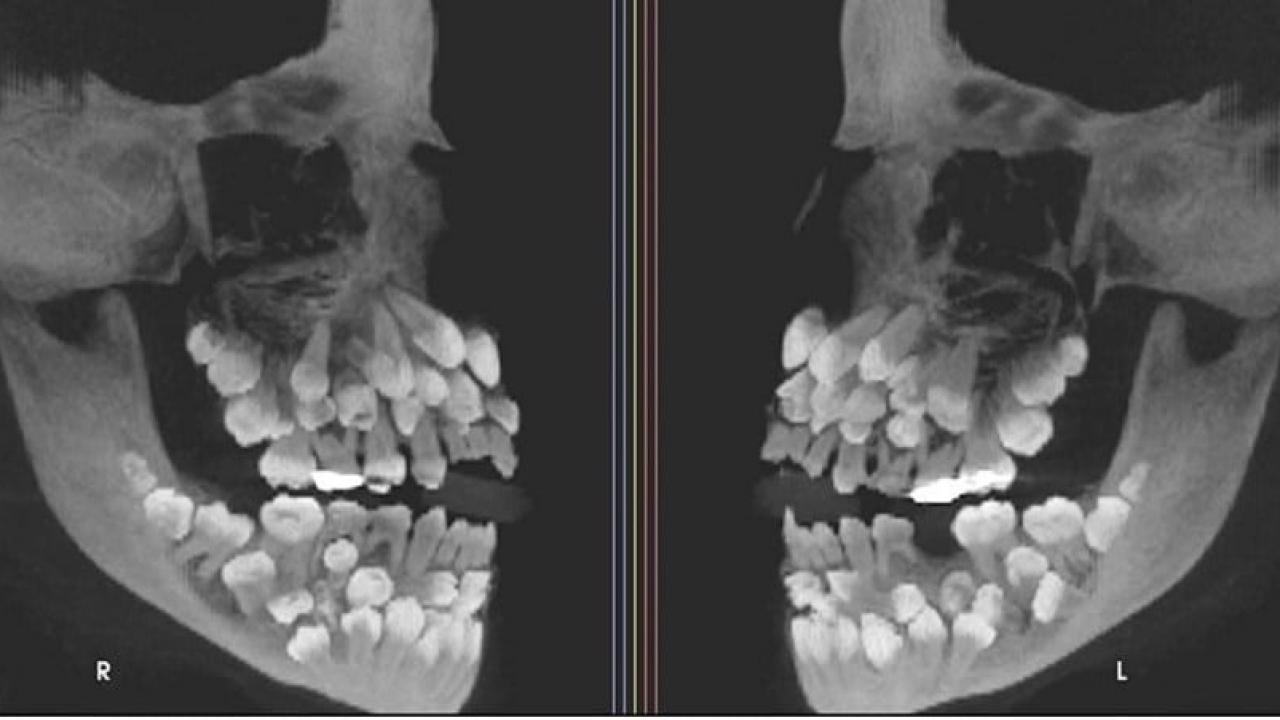

• Brezilya'da eşi benzeri görülmemiş bir vaka ile karşılaşıldı. Geçtiğimiz aylarda yapılan bir açıklamaya göre, 11 yaşındaki bir kız çocuğunun ağzında tam 81 diş tespit edildi.

• Çekilen röntgen filmleri, çocuğun ağzında 18 süt dişi ve 32 kalıcı dişin yanı sıra 31 adet de "süpernümerer" (fazla) diş olduğunu gözler önüne serdi.

• Yetişkinlerde genel olarak 32 kalıcı diş bulunduğu düşünüldüğünde, otuzdan fazla sayıda süpernümerer dişin bir arada bulunması oldukça nadir bir durum.